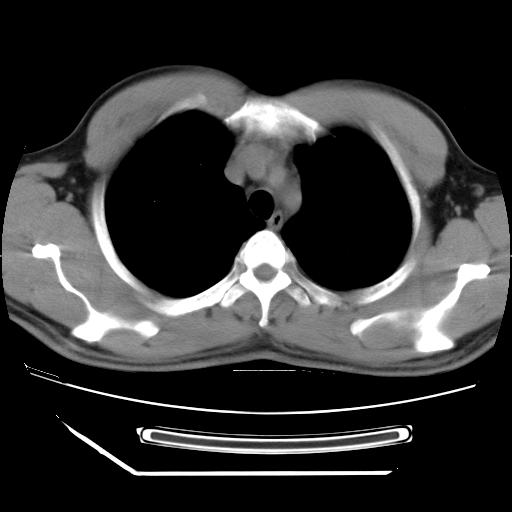

男,38岁,于2009年8月9日晚突发左侧胸痛,今x线提示左下肺阴影,为了明显确诊断,行ct检查,

血常规:嗜酸性细胞增高,单核细胞增高。

纵膈窗